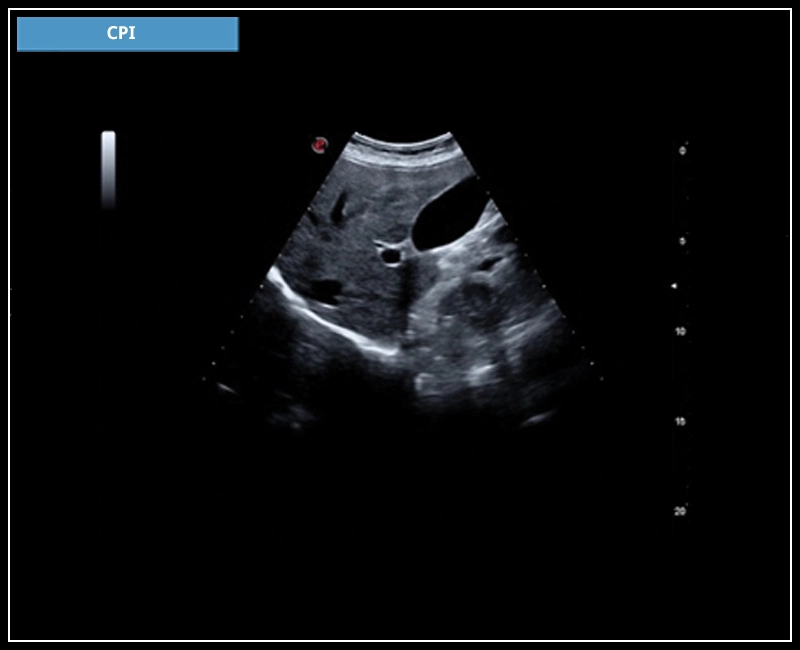

MyLab™X7 - CPI

MyLab™X7 - CPI